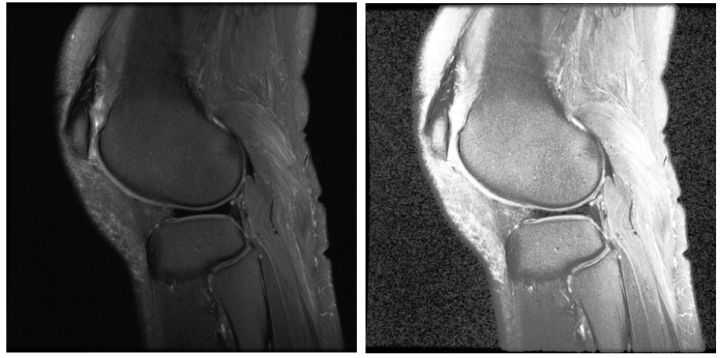

【更多对比的例子】

- 左边是原图

- 中间是HE,有过亮过暗的区域;

- 右边是CLAHE,没有过亮过暗的区域。